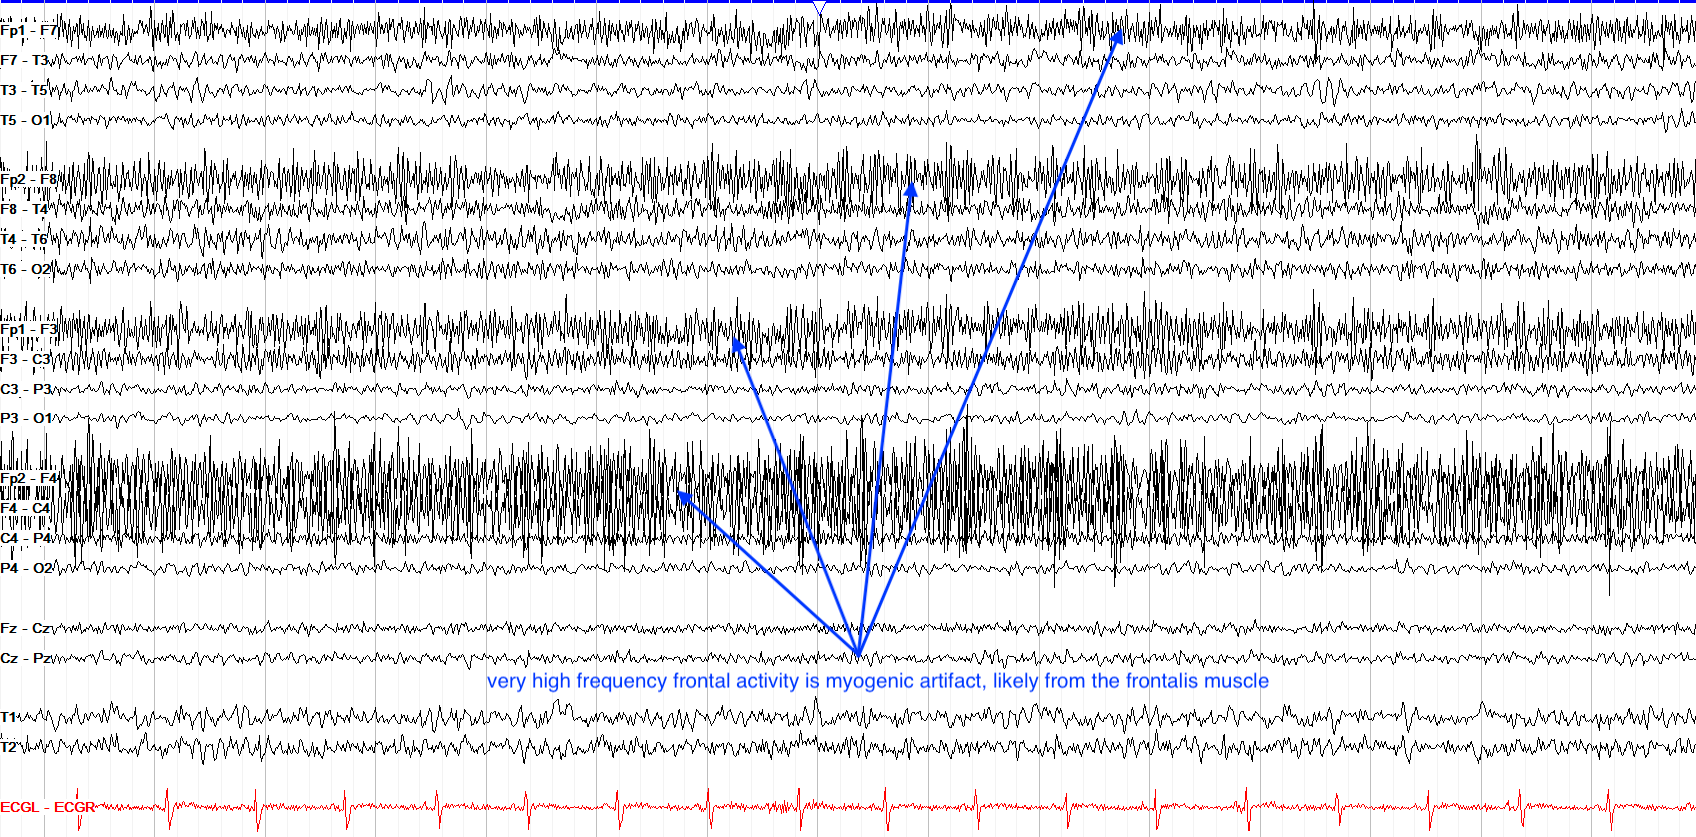

Muscle artifact EEGpedia Movement Artifact Eeg Artifact contamination increases with the intensity of movement. In this article we present a collection of common eeg artifacts and tools for artifact detection, rejection, and removal. In the last decade (since 2010), researchers have started to implement eeg. Artifact contamination increases with the intensity of movement. This article reviews motion artifact removal techniques for wearable eeg and ppg sensor. Movement Artifact Eeg.